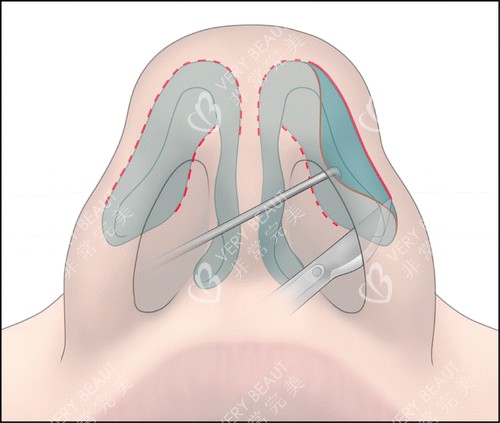

手术过程

手术当天,医院的工作人员都非常热情和贴心,让我紧张的心情得到了较大的缓解。进入手术室后,麻醉师为我进行了麻醉,整个手术过程我没有感觉到任何疼痛。李振医生的操作非常熟练,每一个步骤都严谨细致。虽然我在麻醉状态下,但后来听护士说手术进行得很顺利,用时也比预期的要短一些。